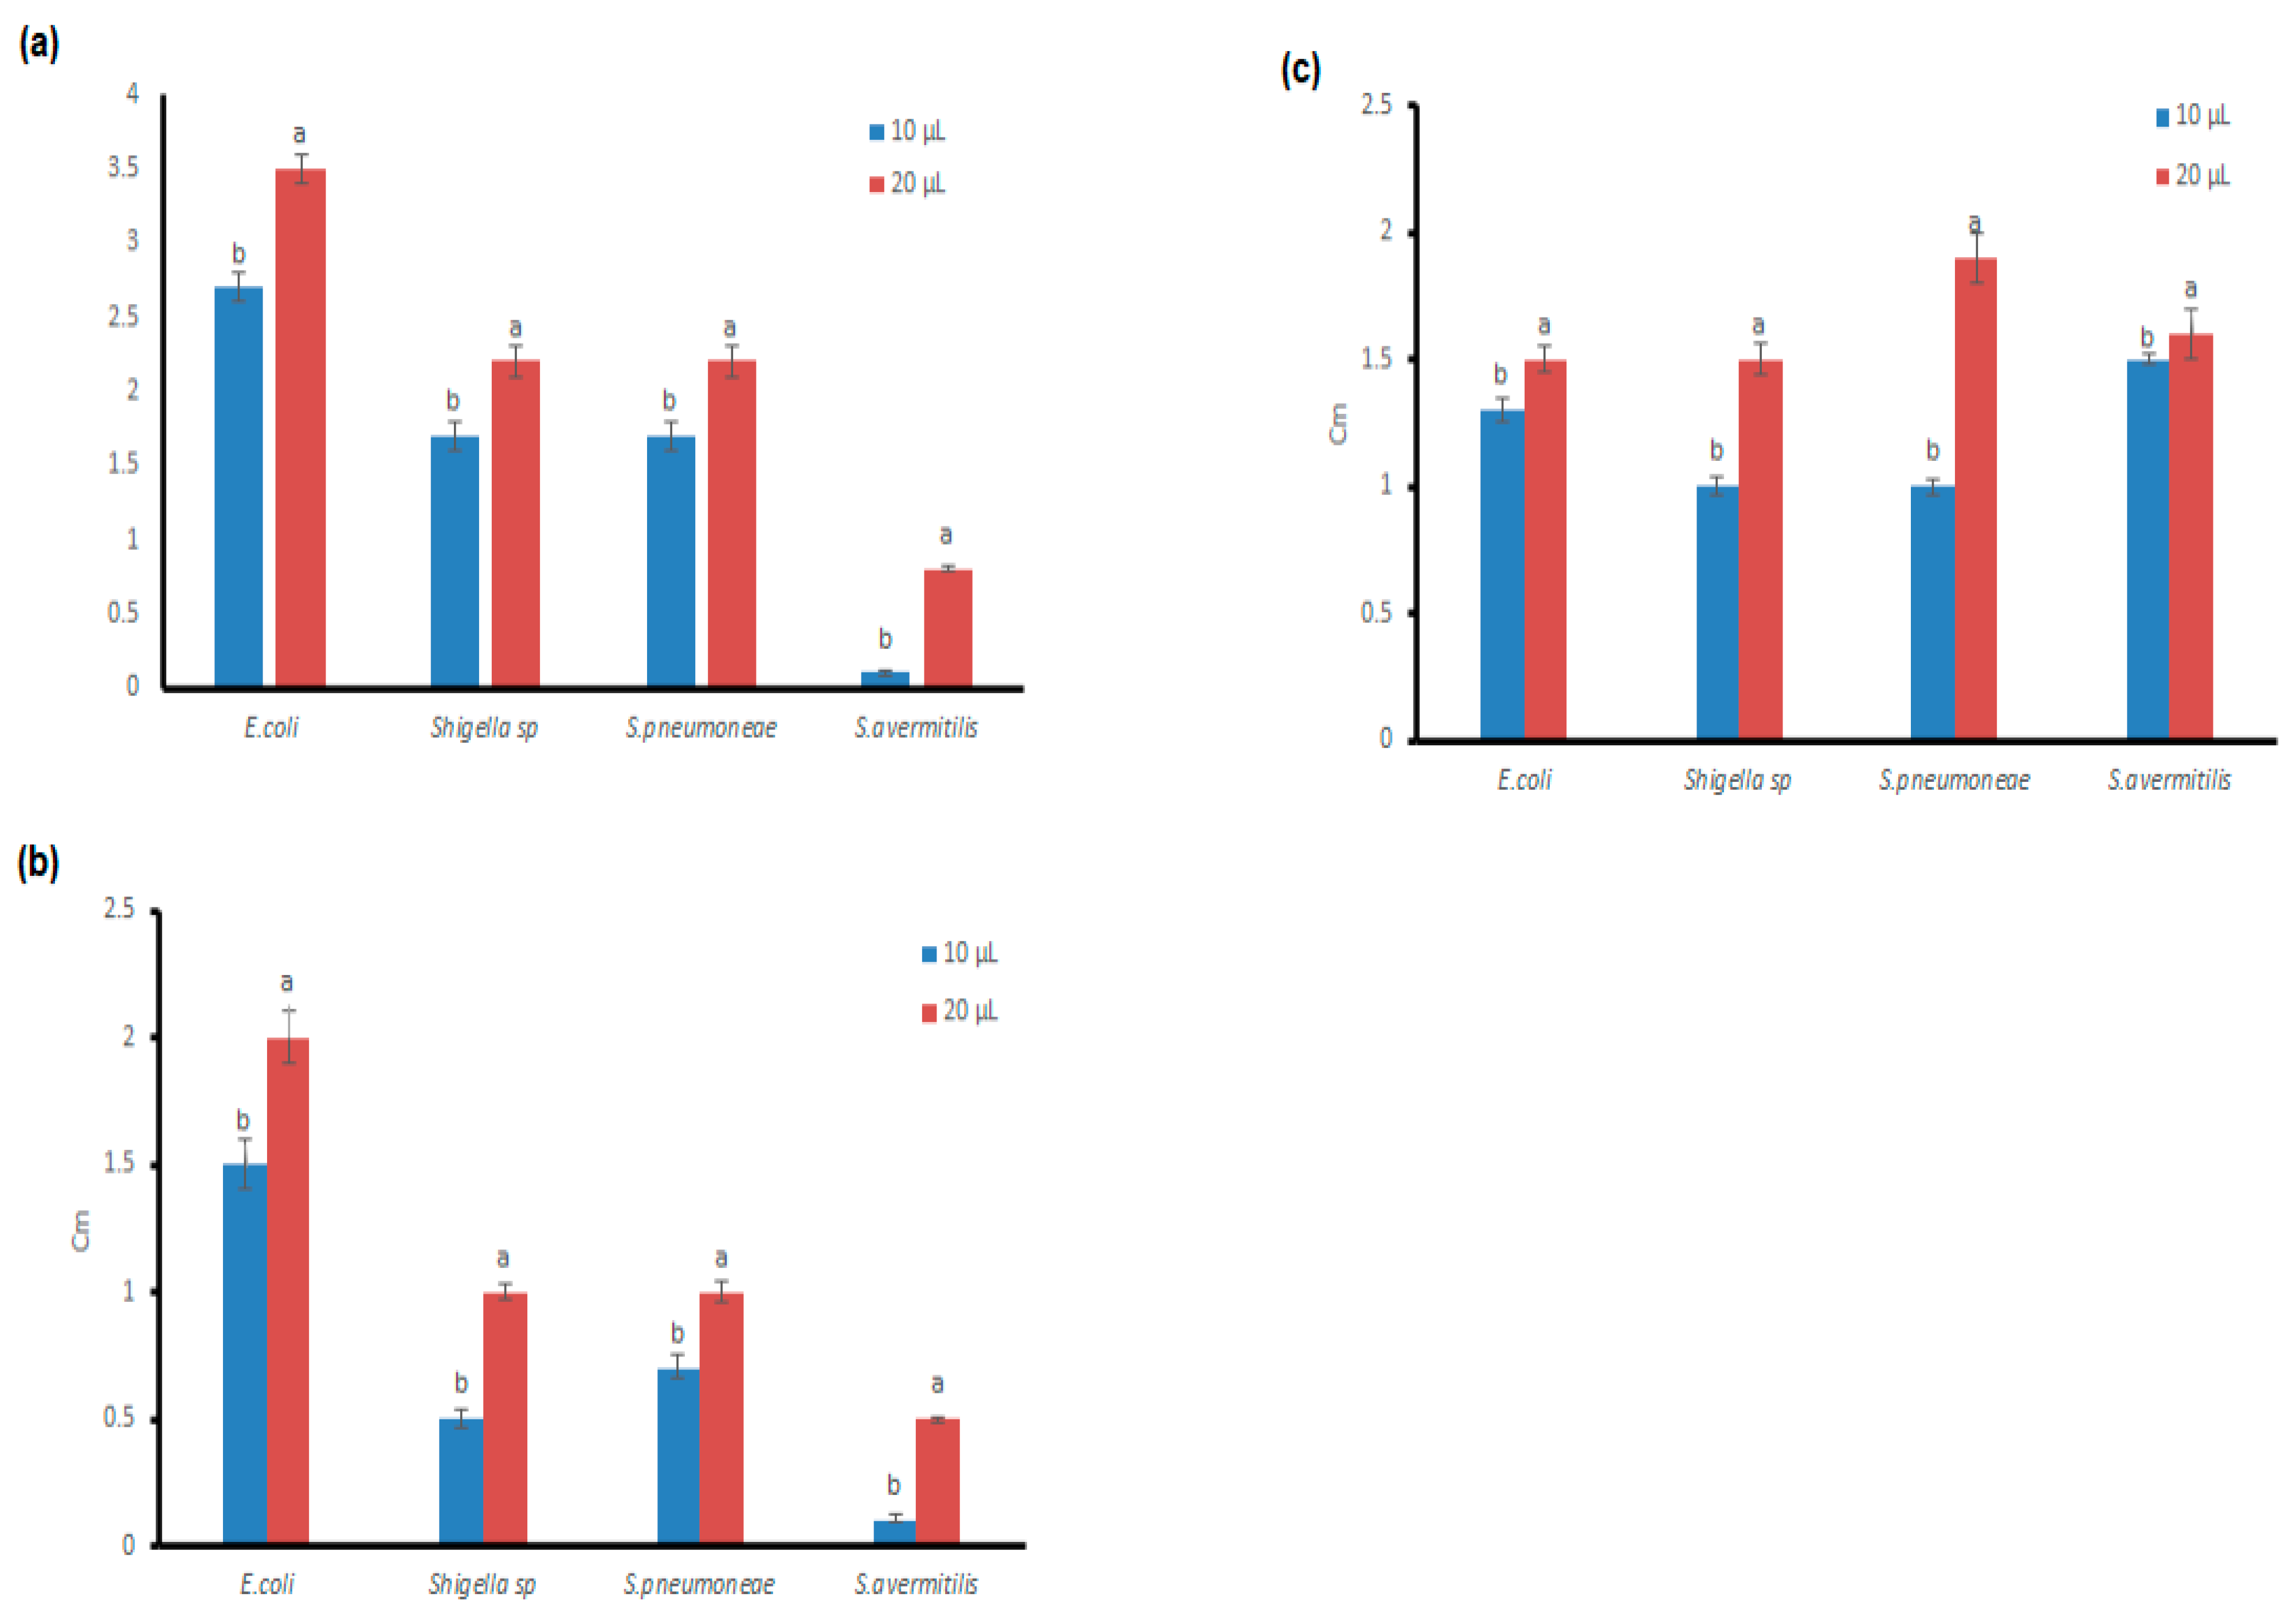

3.4. Antibacterial Potential of the Microfungal Extract